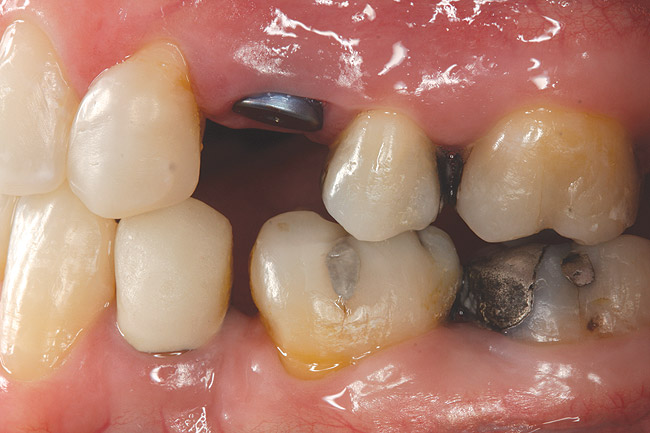

Fig 12 (and Fig 13). Incisors were too upright and had severe incisal wear. He was concerned about esthetics of the worn teeth and his insufficient lip support. Progress photo and panorex 9 months after corticotomies were performed on Nos. 6 through 11. Previous extraction sites were reopened orthodontically to improve function and fill lip support. Incisal edges were restored provisionally with composite resin. Note that despite the creation of adequate spaces to replace missing teeth, there is inadequate room for placement of dental implants because of severe tipping of all the anterior teeth. Osteotomy SFOT may have been a better choice because it would have allowed needed alveoloskeletal correction (without excessive tipping) instead of the primarily dentoalveolar correction common in corticotomy SFOT. Restorative dentist: Brad Jones, DDS.

Figure 12

Fig 13 (and Fig 12). Incisors were too upright and had severe incisal wear. He was concerned about esthetics of the worn teeth and his insufficient lip support. Progress photo and panorex 9 months after corticotomies were performed on Nos. 6 through 11.

Figure 13